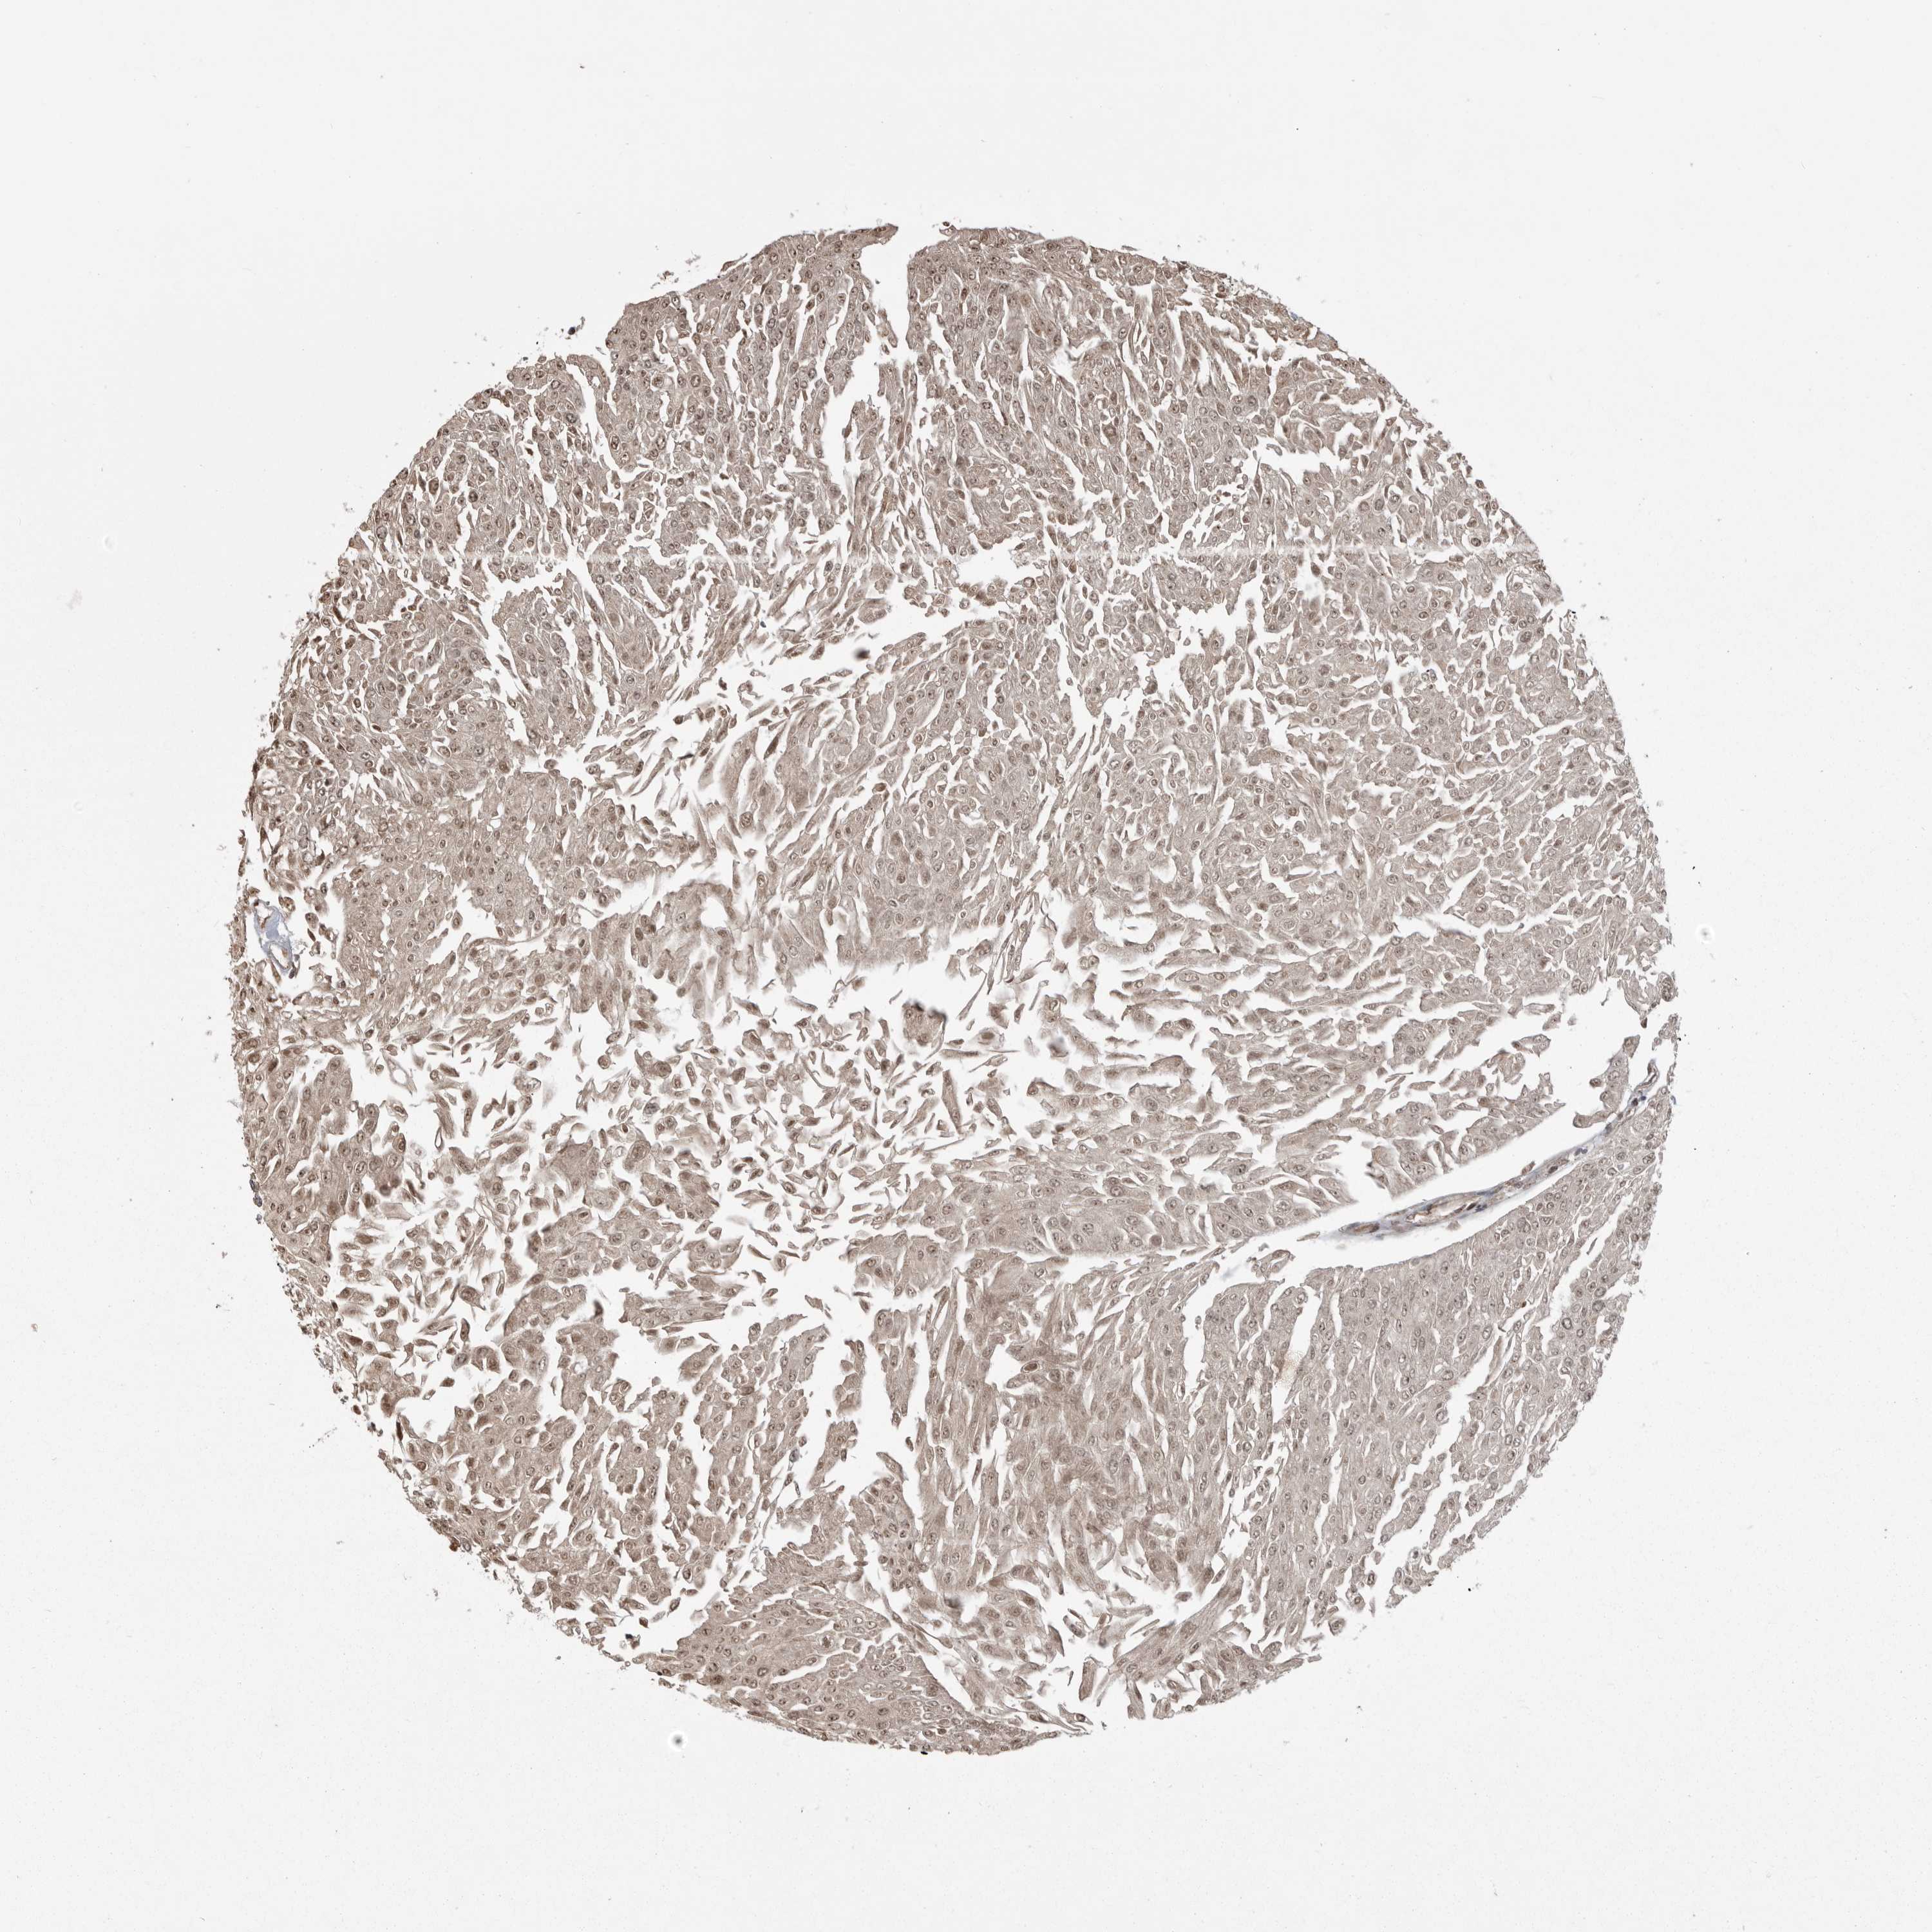

UROTHELIAL CANCER - Protein expressioni

A mouse-over function shows sample information and annotation data. Click on an image to view it in a full screen mode. Samples can be filtered based on level of antibody staining by selecting one or several of the following categories: high, medium, low and not detected. The assay and annotation is described here.

Note that samples used for immunohistochemistry by the Human Protein Atlas do not correspond to samples in the TCGA dataset.

Antibody stainingi

Antibody staining in the annotated cell types in the current human tissue is reported as not detected, low, medium, or high, based on conventional immunohistochemistry profiling in selected tissues. This score is based on the combination of the staining intensity and fraction of stained cells.

Each image is clickable and will lead to virtual microscopy that enables deeper exploration of all samples and also displays staining intensity scores, fraction scores and subcellular localization as well as patient and tissue information for each sample.

Antibody HPA026283

Staining

High

Medium

Low

Not detected

Intensity

Strong

Moderate

Weak

Negative

Quantity

>75%

75%-25%

<25%

None

Location

Nuclear

Cytoplasmic/membranous

Cytoplasmic/membranous,nuclear

Urothelial carcinoma, Low grade

Urothelial carcinoma, High grade